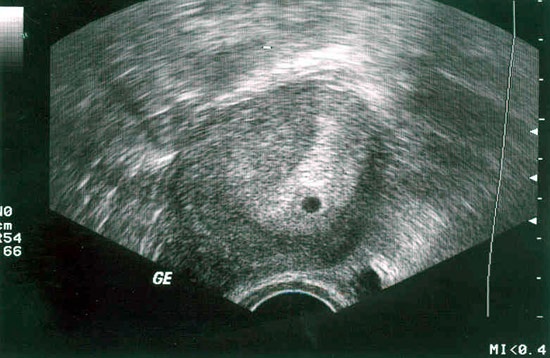

Так выглядит плодное яйцо на сроке 3-4 недели

Плодный мешок, который имеет диаметр всего до 3 мм, датчиком определяется только после 4 недель. А образовавшийся желточный мешок виден специалистам на сроке 5 недель. Когда все явные признаки присутствуют, говорят о наступившей внутриматочной беременности. Практически всегда на этом сроке составляет 5-6 мм, он уже достаточно хорошо визуализируется. Каждый день с пятой по седьмую неделю плодный мешок увеличивается в размерах на 1 мм. Также на пяти неделях уже визуализируется эмбрион, который на тот момент будет иметь размеры около 1-2 мм. Поэтому оплодотворение на УЗИ на ранних сроках визуализировать при наличии можно, но постановка диагноза на сегодняшний день осуществляется другими способами. Основное, на что ориентируются врачи – уровень ХГЧ, но только в крови. Плодное яйцо определяется при ХГЧ, достигающего 1000-2000 мЕд/мл, но рекомендации большинства врачей сводятся к тому, что более-менее безопасное исследование можно проводить, когда уровень ХГЧ превышает 2000 мЕд/мл. Но и это не даст четкой картины о том, как развивается беременность, так как сердцебиение плода можно услышать только тогда, когда его длина достигает 5 мм. Происходит это примерно на 6 или же 7 неделе. В этот срок сердечный ритм соответствует показателям 100 ударов в минуту. Но с увеличением размера плода он учащается до 180 ударов.